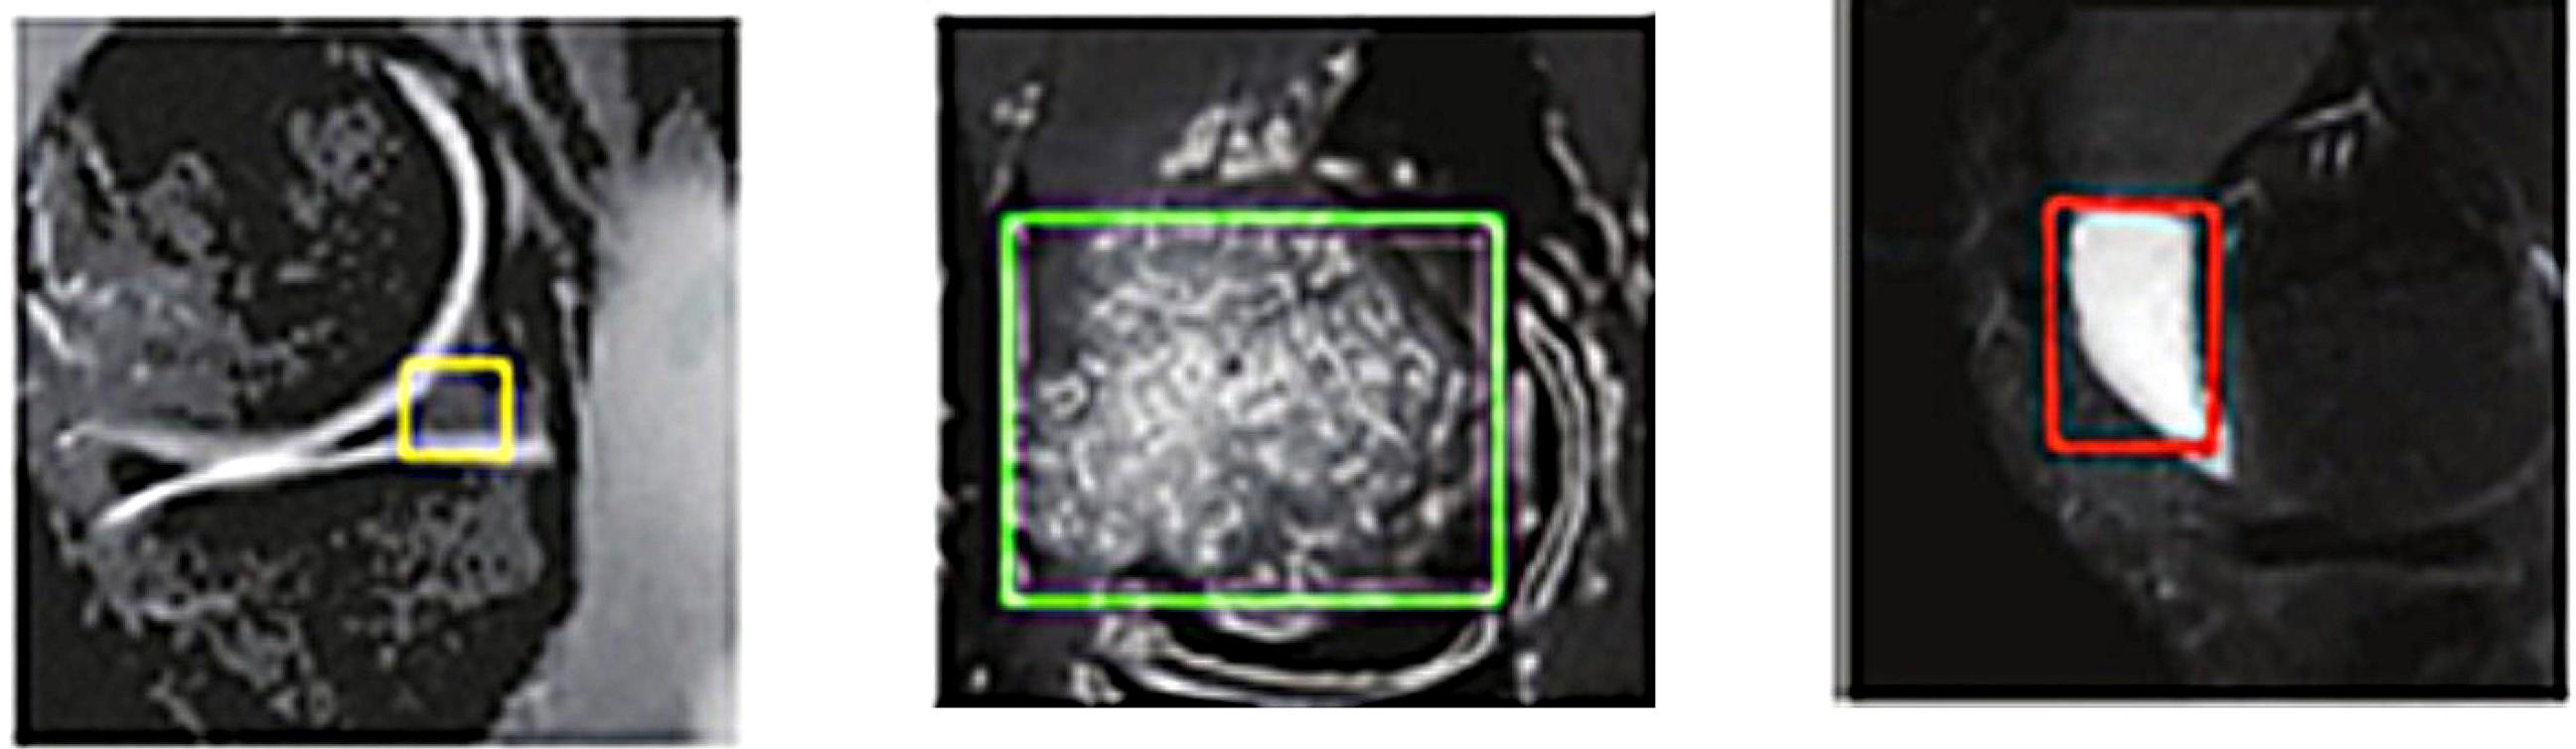

The implementation of features is driven by their ease of use, whereas the dimensions and condition of extracted regions, as potential injurycandidates, are critical factors contributing to their diagnostic significance.36 In contrast, the preceding stage involves the extraction of regions that demonstrate evidence of an injury, whereby solely these characteristics are employed in the determination of the type of injury. The presented illustration, denoted as Fig. 5, serves as an exemplar injuryregion that can be utilized for the purpose of feature extraction with the aim of determining the classification of the injury.

Fig. 5.

An example of an injury identified for feature extraction.